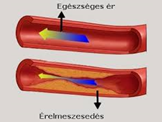

Az érelmeszesedés nem jár együtt a korral – már huszonéveseknél is kialakulhat. Az érfalakban keletkező lerakódások és az érfalak merevvé válása nem időskori jelenség. Hol vannak az érelmeszesedés tipikus helyei? Az érelmeszesedés kialakulása.

Homocisztein káros hatása az érelmeszesedésre. Az érfal (endothelium) sérülésének oka. Az érfal (endothelium) sérülésének oka. Az egészséges endothel működésében központi szerepet játszik a nitrogén-monoxid (NO). Érelmeszesedés megelőzése, csökkentési lehetősége, kezelése. Rezveratrol, fokhagyma, Golden Yacca Plus, K2 vitamin kedvező hatása. Sztatin gyógyszer hatása az érelmeszesedésre.

Szintetikus gyógyszerek hatása. Érelmeszesedés megelőzése, csökkentési lehetősége, kezelése